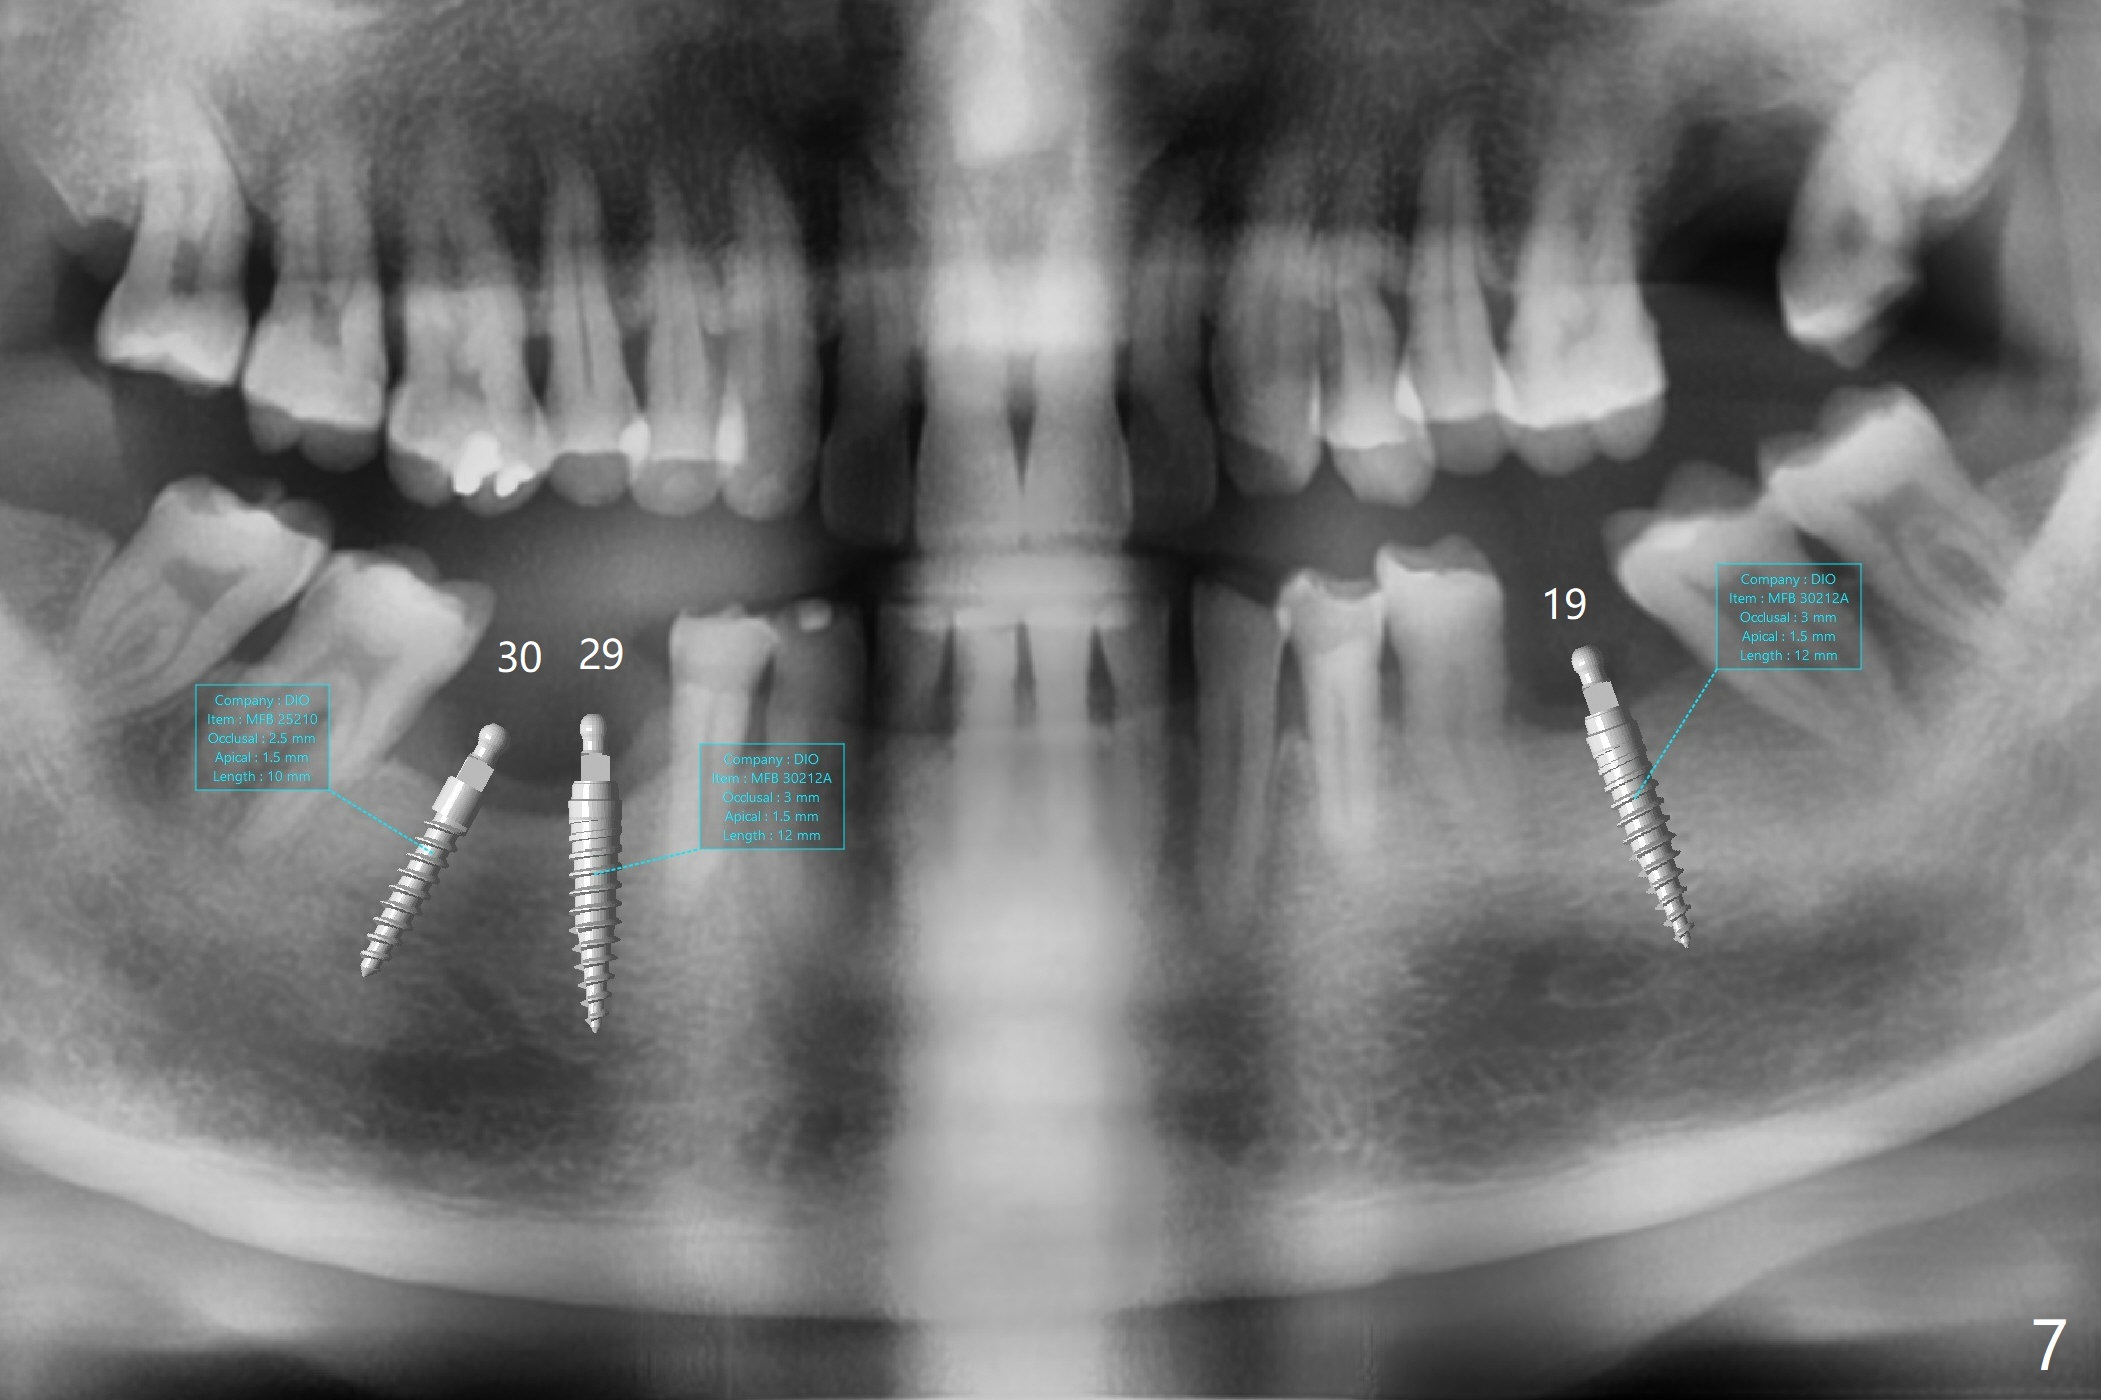

The patient would like to have implants to replace the lower RPD if the 1st surgery turns out to be successful. Due to the presence of the Mental Loop (Fig.1 red dashed line) and thin bone at #29 and 30 (Fig.3,4), 1-piece implants seem to be a good option. A 2-piece implant can be placed at #19 (Fig.5). After cementation of #15 implant crown, reanalysis of CT reveals that a 3x12 mm 1-piece implant is more appropriate at #19 with a space less than a premolar (Fig.6). With 2 of narrow short implants at #29 and 30, violation of the Mental Loop is less likely to happen than a single one in the middle of the edentulous area (Fig.7).